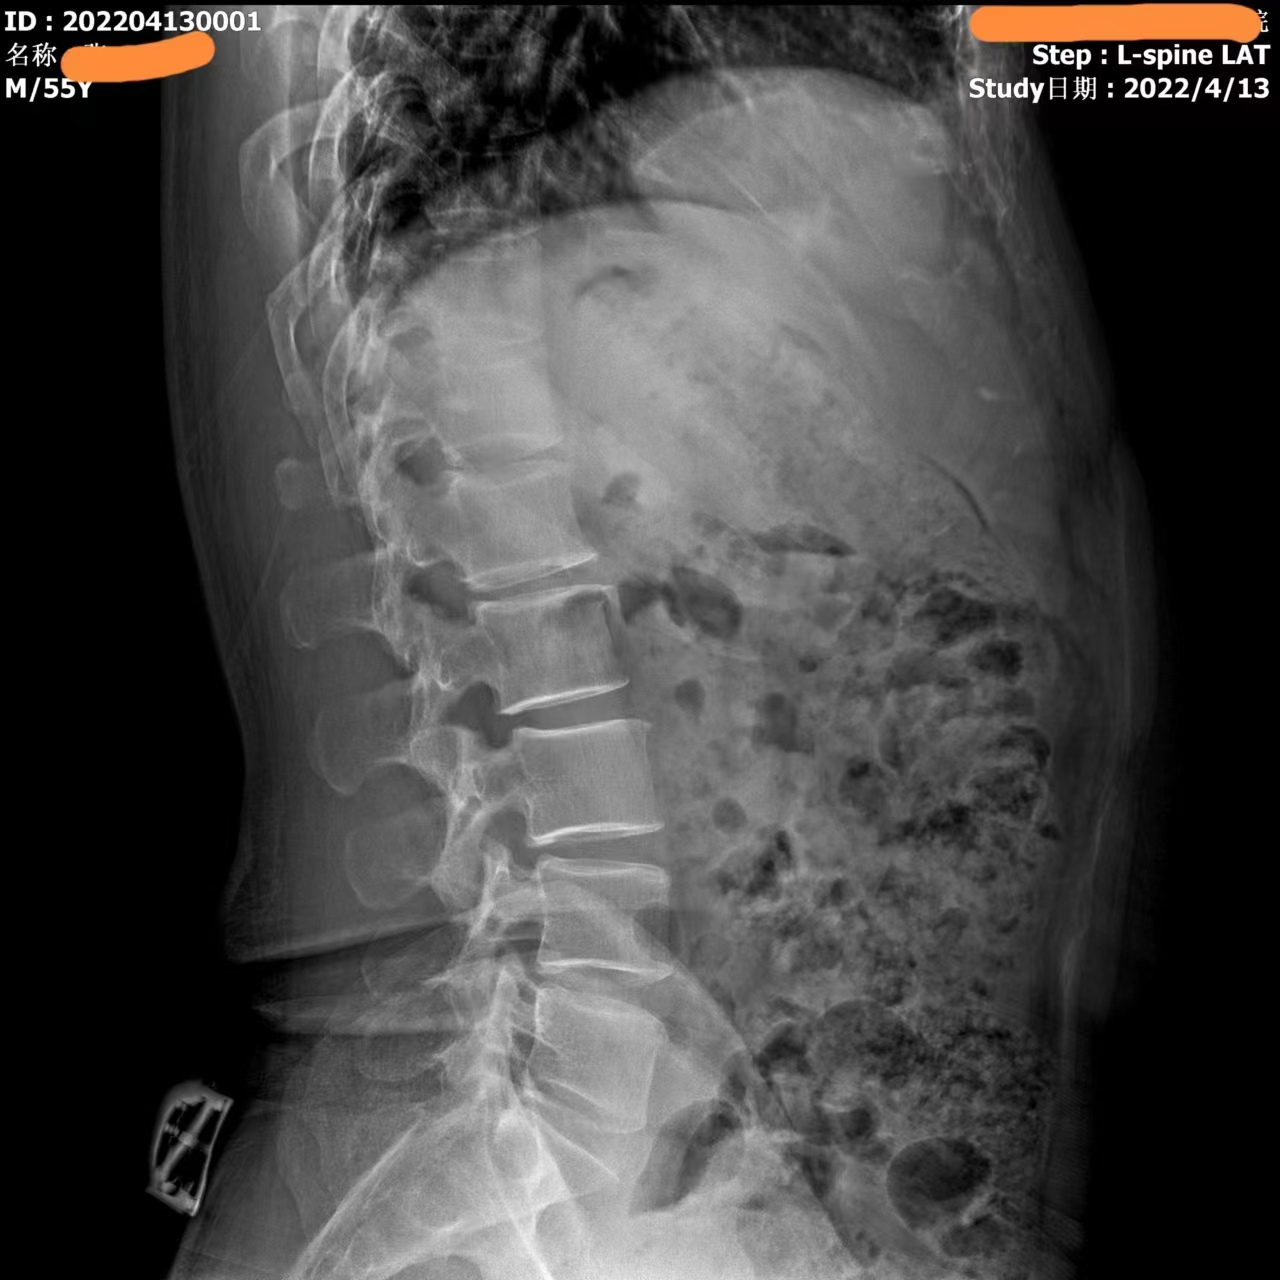

Видео с этого устройства выглядит следующим образом: